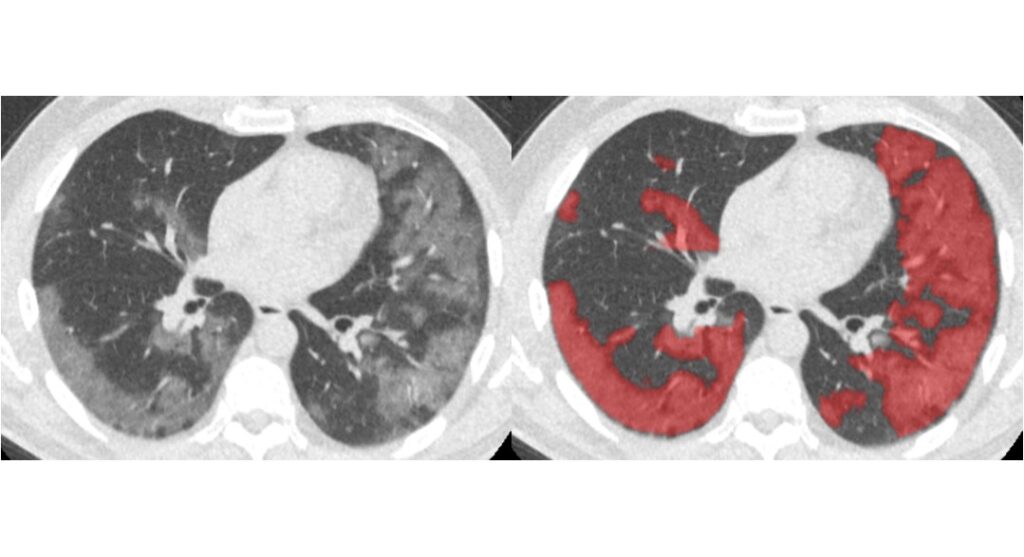

We have launched CAD4COVID-CT

We are proud to launch CAD4COVID-CT, our artificial intelligence software for the analysis of COVID-19 on CT scans.